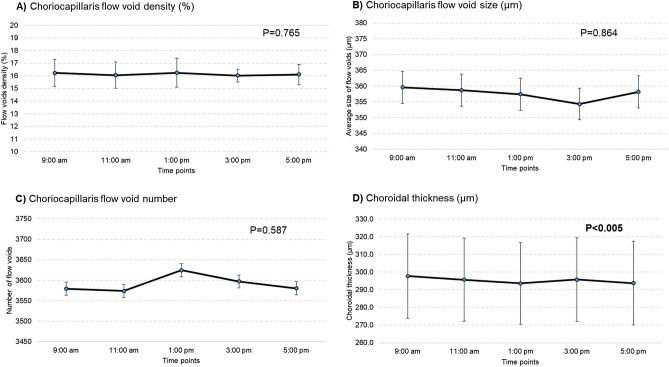

Table 1 shows the change in choriocapillaris flow voids and choroidal thickness throughout the day. The features of choriocapillaris flow voids did not change significantly over time on the first visit, where the density was 16.2 ± 1.1%, average size of flow void was 359.6 ± 26.6 µm and number was 3,579.4 ± 151.5 (P > 0.05; Table 1 and Fig. 1A–C). These findings remained similar for the second visit. In terms of choroidal thickness, there was a small but statistically significant decrease in the thickness over time (Table 1 and Fig. 1D). On average, the choroid was thickest at 9:00 am at 297.7 ± 92.1 µm, followed by 295.7 ± 91.0 µm at 11:00 am, 293.6 ± 89.5 µm at 1:00 pm, 295.7 ± 91.8 µm at 3:00 pm and thinnest 293.8 ± 91.5 µm at 5:00 pm (P < 0.005) for the first visit. These findings remained similar for the second visit (P < 0.002). Figure 2 shows an example of a patient where the thickness of the choroid was impacted by diurnal variation, while the density of the choriocapillaris flow voids remained unaffected.

Figure 1.

There was no diurnal variation on any of the choriocapillaris flow voids features (A–C; P > 0.05). Diurnal variation had an impact on choroidal thickness, where it was thickest in the morning and thinnest in the evening (D; P < 0.005). P values were obtained with repeated-measures ANOVA, where within-subject factor (time of visit) was adjusted.